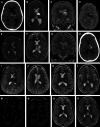

Background and objectives: Hemorrhagic subcortical vascular lesions such as cavernous malformations (CM) and arteriovenous malformations (AVM) can be neurologically devastating. Conventional open surgical resection is often associated with additional morbidity. The BrainPath® (NICO Corp.) transsulcal tubular retractor system offers a less-invasive corridor to deep-seated lesions. Our objective was to describe a single-center experience with the resection of subcortical hemorrhagic vascular lesions in adult and pediatric patients using the BrainPath® system.

Methods: The departmental database was queried for patients who underwent resection of a hemorrhagic CM, AVM, or cerebral aneurysm through the BrainPath® tubular retractor system between January 2017 and September 2021. All patients underwent either postoperative MRI (for patients with CM) or digital subtraction angiography (for patients with AVM or aneurysm). Demographic and clinical characteristics, preoperative and postoperative imaging features, operative details, and surgical and clinical outcomes were extracted through a retrospective review of the medical records.

Results: Fourteen patients (mean [SD] age 32.3 [23.9] years; 7 (50%) female) underwent BrainPath®-based resection of a deeply seated CM (n = 7), AVM (n = 6), or ruptured cerebral aneurysm (n = 1). The mean maximal lesion diameter was 21.5 (12.6) mm. The mean operative time was 134 (53) minutes. Residual lesion was present in 2 patients, both of which underwent repeat BrainPath®-assisted surgery for complete resection. All lesions were completely resected or obliterated on postoperative MRI or digital subtraction angiography. At a mean follow-up of 4.1 (1.1) years, the median modified Rankin Scale score was 1 (range 0-6).

Conclusion: In a well-selected cohort, we show the effective use of BrainPath® tubular retractors for resection or obliteration of subcortical hemorrhagic vascular lesions. This report further exemplifies the expanded role of the endoport system beyond that of intracerebral hemorrhage and tumor. Further study will elucidate the impact of this less-invasive brain retraction technique on clinical outcome in patients with vascular lesions.